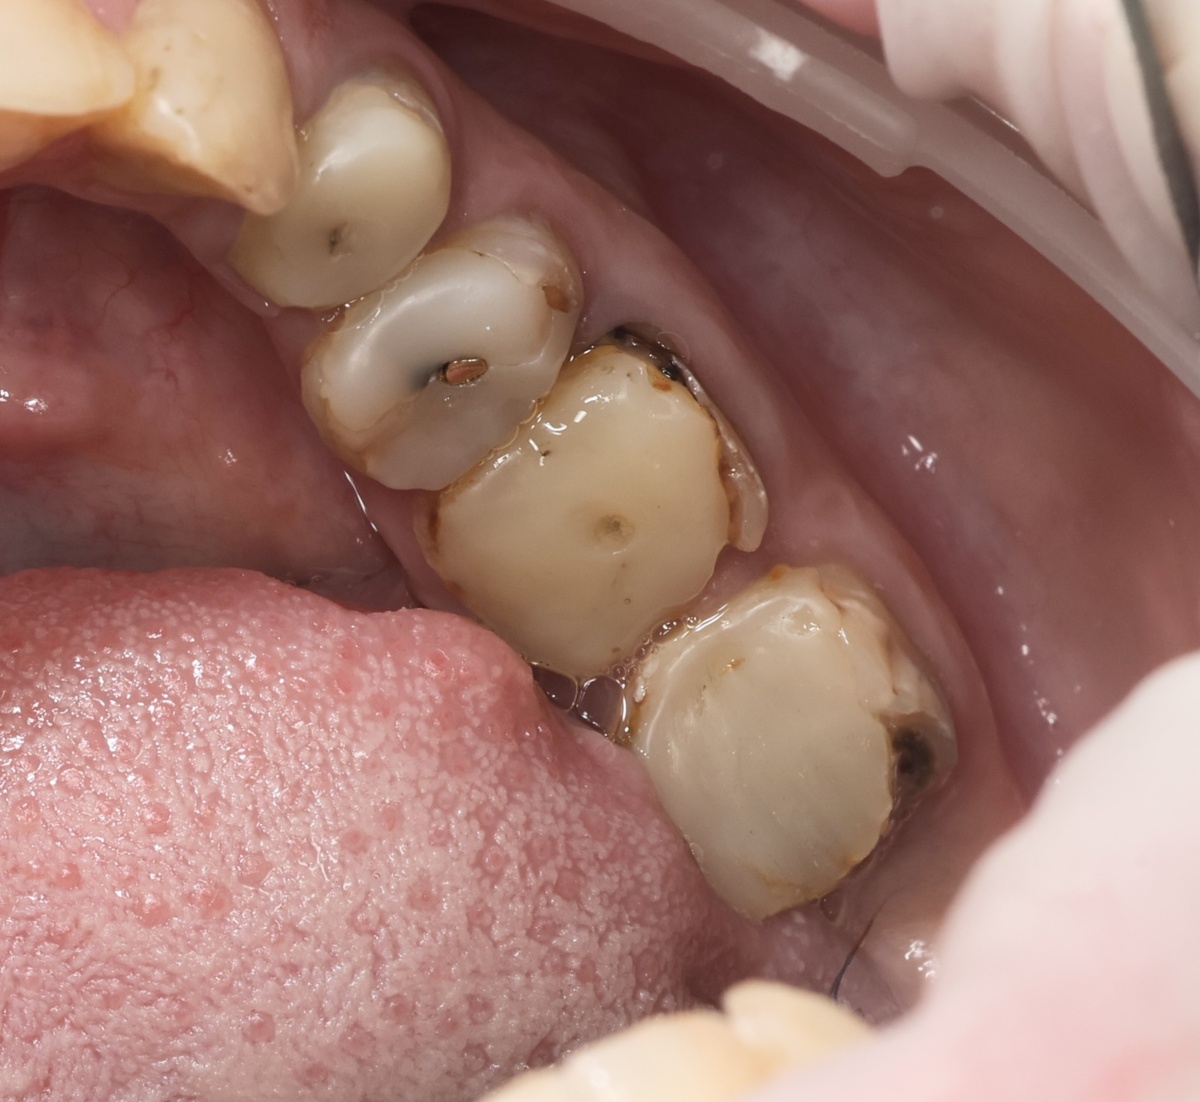

Вот сразу же видно - человек зубами занимался, стоматолога не игнорировал, на зубы свои не забивал. Но... Сами оцените состояние 3.4, 3.5, 3.6, 3.7 - весь левый нижний сегмент:

Формально - всё пролечено (не в нашей клинике). Стоят пломбы, проглядывают сквозь материал штифты. Но кто назовёт это здоровым видом? Кто скажет, что это - годный результат? Что-то, отдалённо похожее на билдапы, только сколотое, разбитое. Кариес, разрушения, пломбы без прилегания. И так почти везде... И такое - у многих. Зубы без коронок, когда коронки были нужны, со временем разрушаются. Но терапевты некоторые, почему-то, короновать зубы не рекомендуют, да и не все пациенты на коронацию согласны. И ещё вишенка на торте - качественную ортопедическую работу наблюдать приходится редко, увы.

Не массовое явление - качество.

Почему не стоит оставлять зубы с огромными пломбами "голыми" без коронок надолго - выясним в статье данной.

А сегодня разберём зуб 3.4. Он, кстати, не самый плохой из перечисленных. Но тоже показательный.